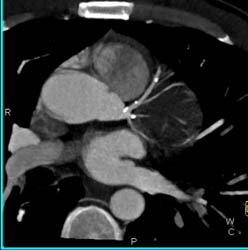

Aneurysm of Left Circumflex Coronary Artery